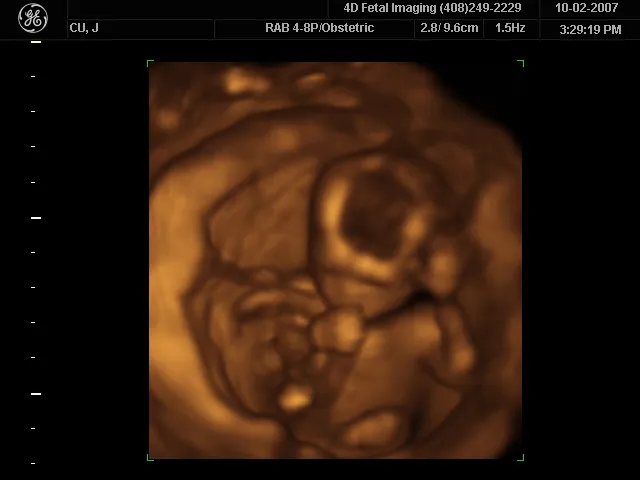

How much detail can ultrasound reveal? The image in Figure 17.43 is typical of low-cost systems, but that in Figure 17.44 shows the remarkable detail possible with more advanced systems, including 3D imaging. Ultrasound today is commonly used in prenatal care. Such imaging can be used to see if the fetus is developing at a normal rate, and help in the determination of serious problems early in the pregnancy. Ultrasound is also in wide use to image the chambers of the heart and the flow of blood within the beating heart, using the Doppler effect (echocardiology).

This is an image of a 3D ultrasound scan of the fetus showing an unborn baby sucking its thumb.

Figure 17.44 A 3D ultrasound image of a fetus. (credit: Jennie Cu, Wikimedia Commons)